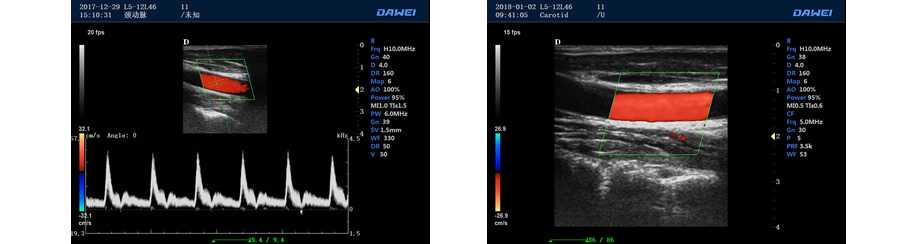

多普勒模式

具有PW脈沖波多普勒和CW連續(xù)波多普勒

取樣容積大小,可視可調(diào)

采樣角度校正:-30-80度

脈沖重復(fù)頻率多段可調(diào)

實時自動多普勒包絡(luò)描述及自動測量與分析

外周血管 多普勒血流測量與分析